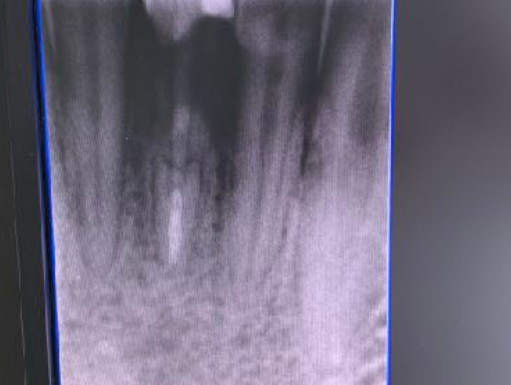

| Intraoral x-ray app: Vix-Win Guidizzolo x-ray | CT scan: no |

| Extractive situation: Immediate post-extraction implant with immediate loading. | Density according to Misch: D2 |

| Drill sequence: Lanceolate cutter only | Sequence of taps: tap diameter 4 mm |